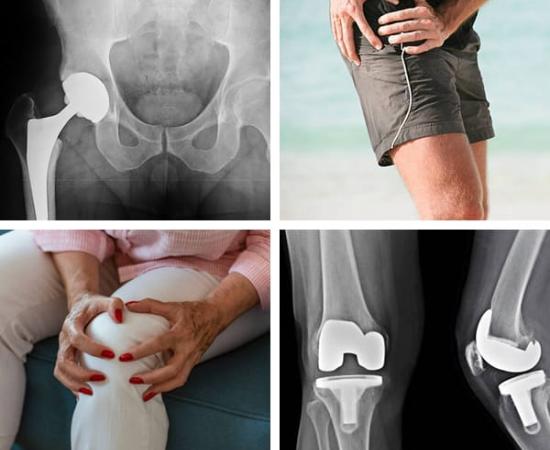

Oporavak kuka, koljena i bedra nakon operacije: Oporavak uvijek počinje vjerom da je moguć